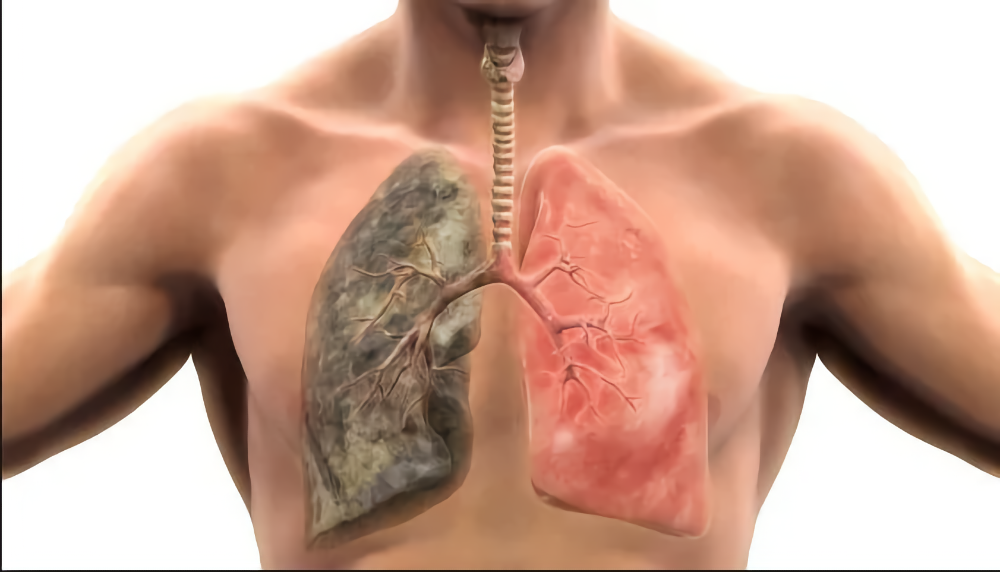

По словам специалиста, положительные изменения и вправду возможны. Так, несмотря на то, что не всегда удается полностью восстановить структурные изменения лёгких, специалистам удаётся значительно улучшить их здоровье и функцию. Для этого, правда, пациенты вынуждены полностью отказаться курения.

При этом, отметил Зинченко, степень восстановления органа зависит от общего состояния здоровья, продолжительности курения и существующих повреждений.

Важно понимать, что лёгкие обладают свойством самоочищения. Также в течение первого дня после отказа от сигарет, у человека снижается уровень угарного газа в крови, а уровень кислорода приходит в норму.